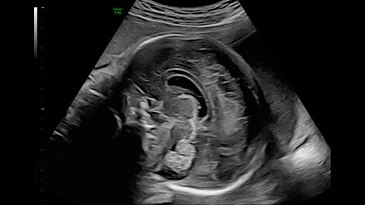

Fetal brain with C2-9 probe and HDRes